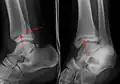

A triplane fracture of the ankle as seen on plain X-ray

There are three x-ray views in a complete ankle series: anteroposterior (AP), lateral, and oblique (or "mortise view"). The mortise view is an AP x-ray taken with the ankle internally rotated 15-20 degrees since the foot is naturally externally rotated relative to the ankle.[8] In addition to these views, a full-length view of the tibia and fibula may be necessary to evaluate for injuries to the proximal fibula associated with Maisonneuve fractures.

On X-rays, there can be a fracture of the medial malleolus, the lateral malleolus, and/or of the anterior/posterior margin of the distal tibia. The posterior margin (known as the posterior malleolus) is much more frequently injured than the anterior aspect of the distal tibia. If both the lateral and medial malleoli are broken, this is called a bimalleolar fracture (some of them are called Pott's fractures). If the posterior malleolus is also fractured, this is called a trimalleolar fracture.

- Triplane fractures are a special type of fracture that involves the immature skeleton. It has a coronal plane in the metaphysis, an axial plane in the physis, and a sagittal plane in the epiphysis.[14]